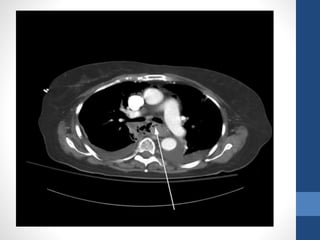

Imaging :

• Computed tomography (CT) scanning and

ultrasonography may be indicated for the

evaluation of liver disease with cirrhosis,

cholecystitis with hemorrhage, pancreatitis

with pseudocyst and hemorrhage,

aortoenteric fistula, and other unusual

causes of upper GI hemorrhage.

• Nuclear medicine scans may be useful in

determining the area of active hemorrhage

• Computed tomography(CT) scanning and ultrasonography may be indicated for the evaluation of liver disease with cirrhosis, cholecystitis with hemorrhage, pancreatitis with pseudocyst and hemorrhage, aortoenteric fistula, and other unusual causes of upper GI hemorrhage. • Nuclear medicine scans may be useful in determining the area of active hemorrhage